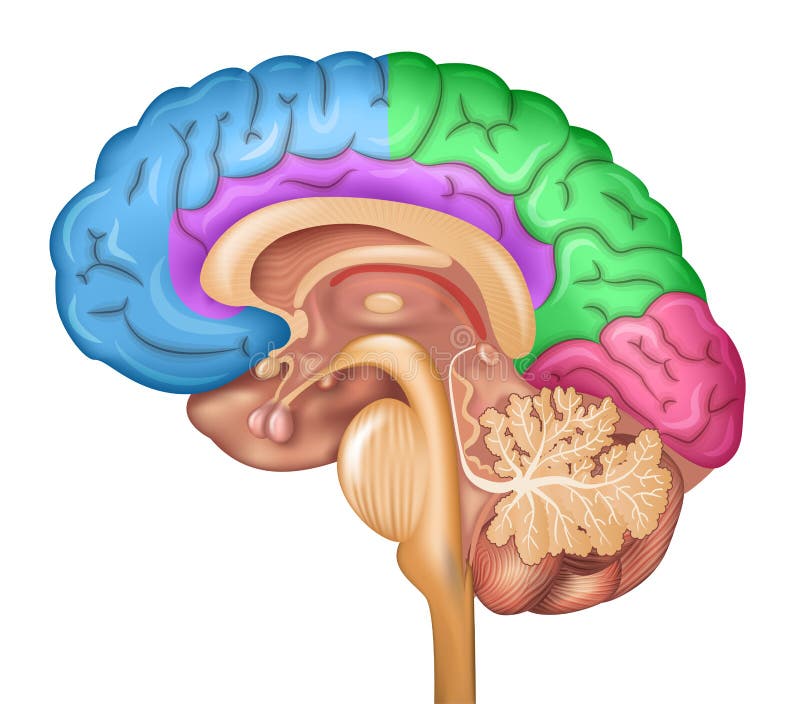

έννοια της τεχνητής νοημοσύνης. άνθρωπος-εγκέφαλος με σύμβολο τεχνητής νοημοσύνης.